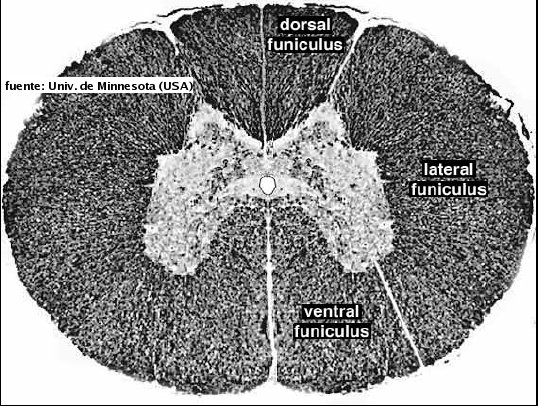

En una sección transversal, en la médula espinal se observa:

Materia blanca (derivada de la capa marginal del tubo neural). Está compuesta por concentraciones de fibras mielinizadas, gliocitos y por escasa cantidad de capilares. Sus regiones se denominan como funículo dorsal, ventral y lateral, con la comisura blanca.